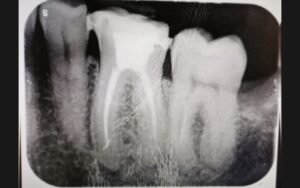

Caso clinico di devitalizzazione non corretta

In questo caso possiamo osservare un caso di devitalizzazione non corretta; presso il nostro studio specializzato abbiamo proceduto con il ritrattamento endodontico.